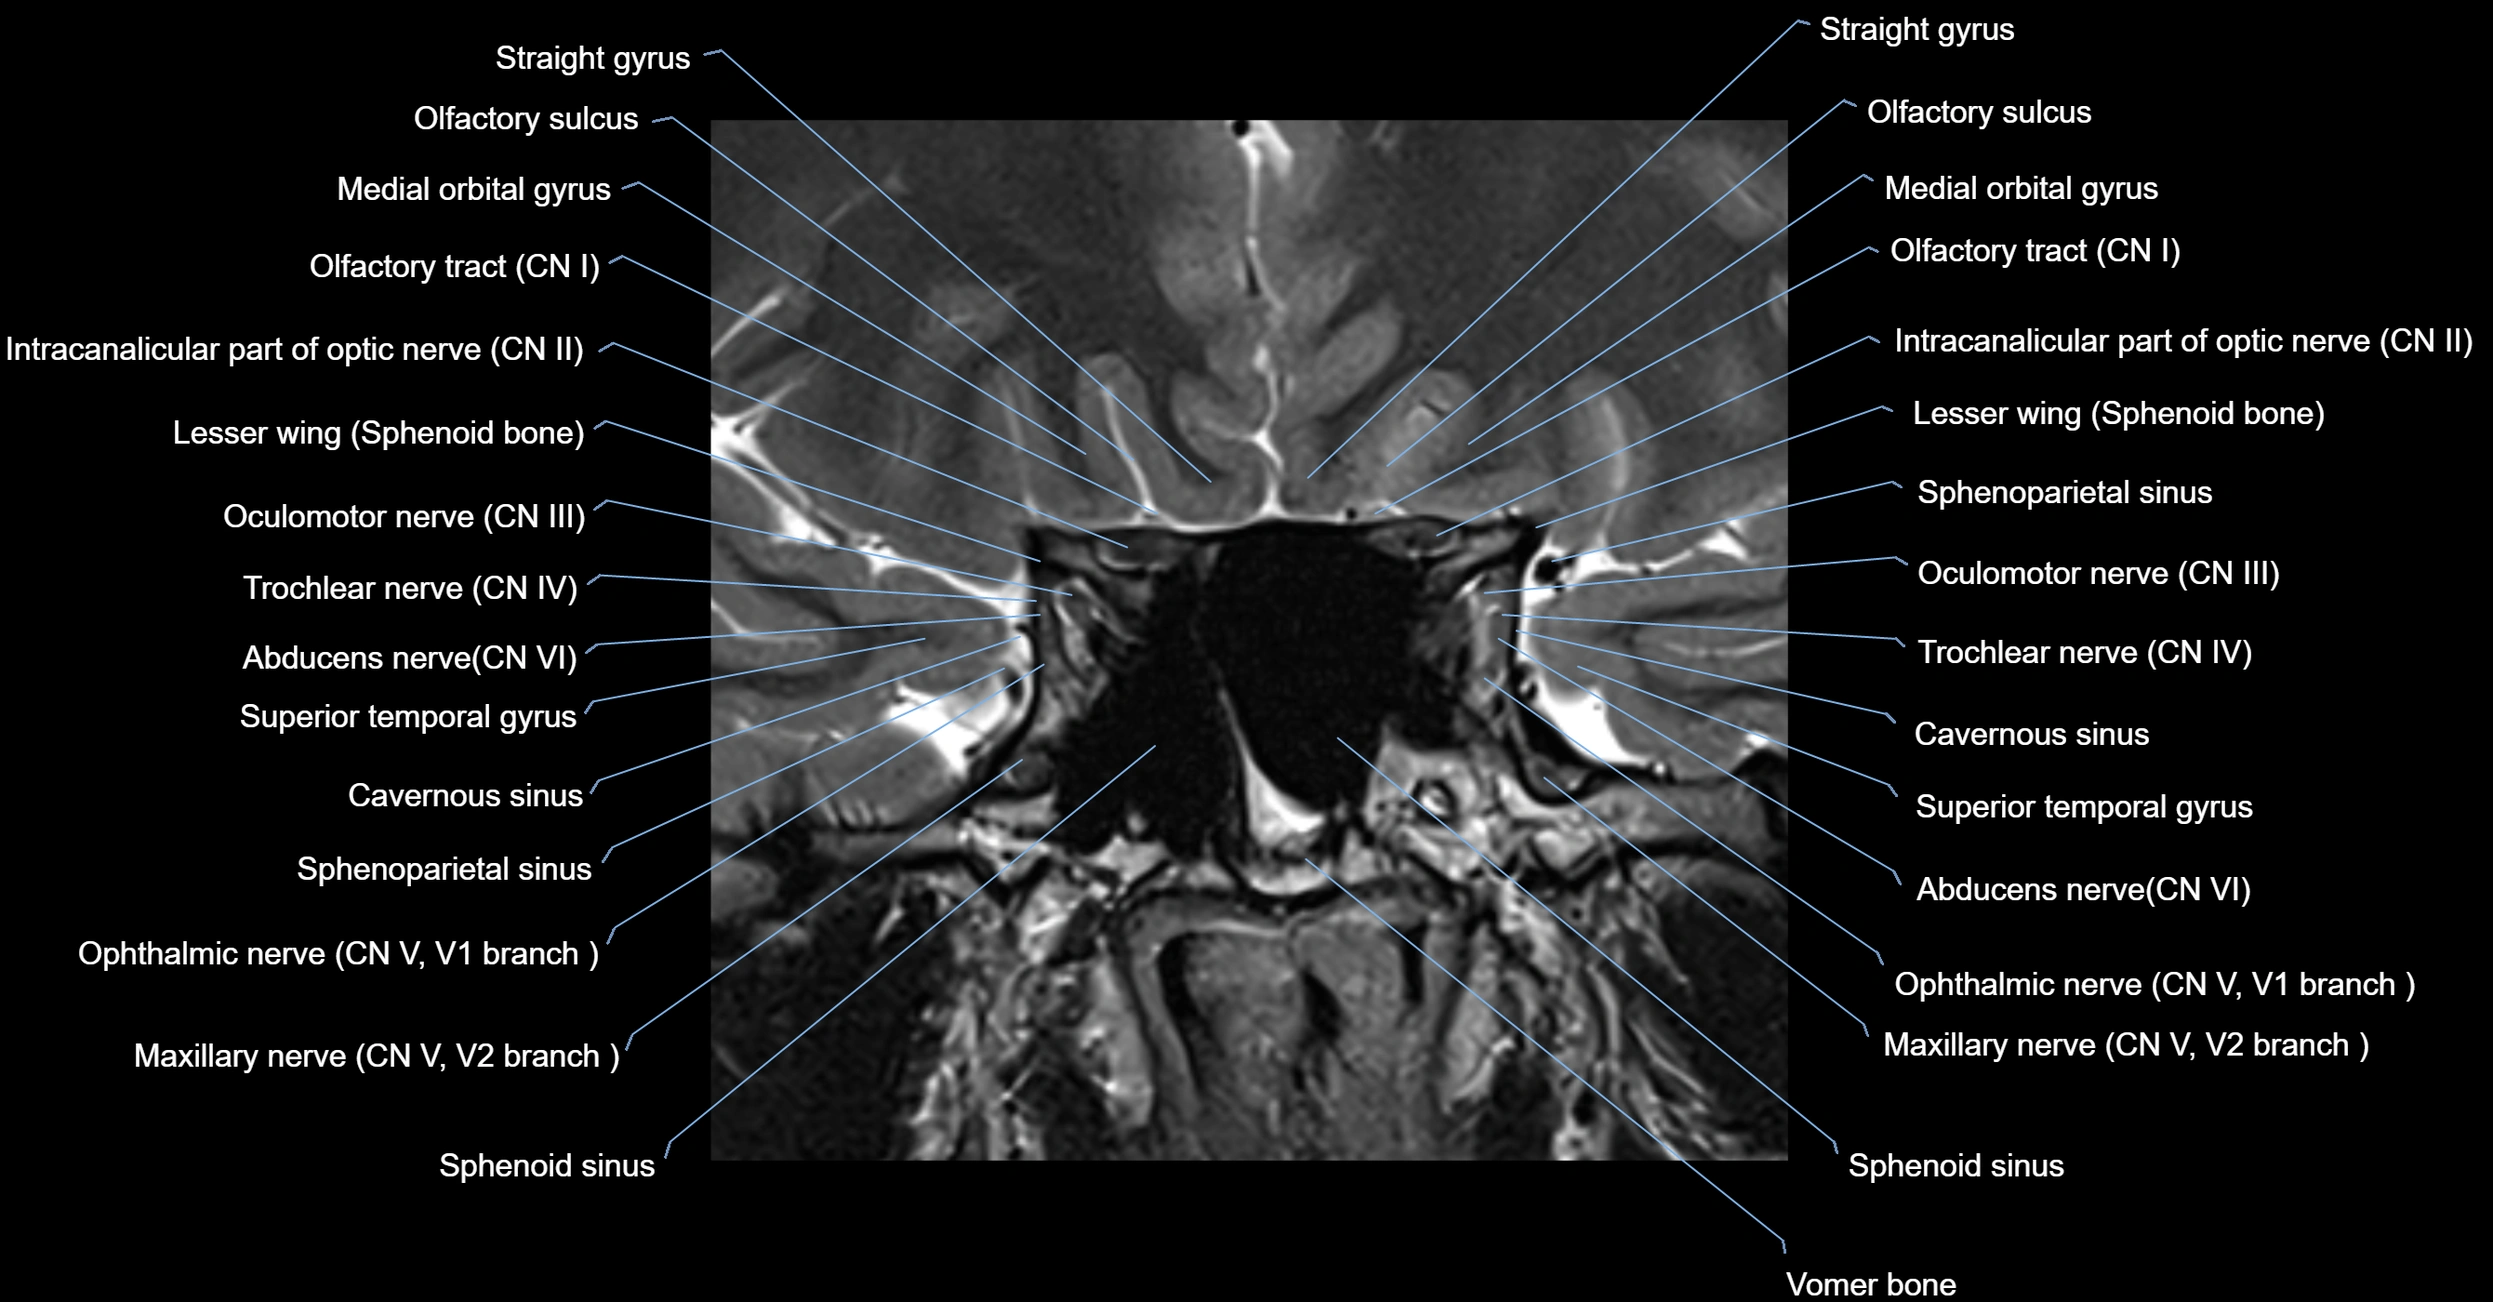

MRI Appearance

-

The abducens nerve is a small, thin, linear structure

Best visualized on high-resolution T2-weighted 3D MRI sequences (e.g., FIESTA or CISS)

Seen as a hypointense (dark) line running from the brainstem at the pontomedullary junction, traversing the prepontine cistern, and entering Dorello’s canal under the petrosphenoidal ligament, then into the cavernous sinus, and finally the orbit

May be challenging to visualize in standard MRI due to its small size

Pathology may be inferred by absence, displacement, or enhancement of the nerve

MRI images